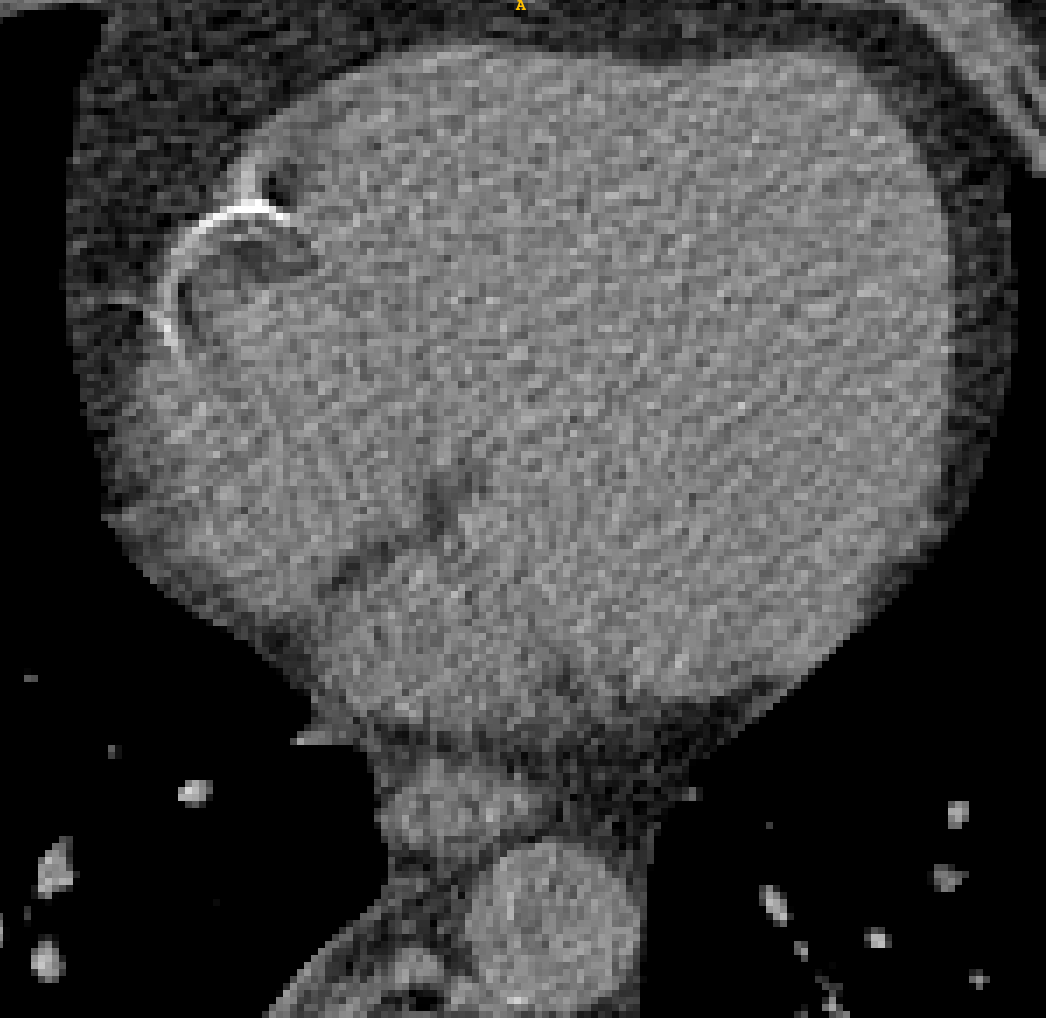

TABLE V: Visualization result on SegTHOR. Gray image registration result(row 1-2) shows the fitting ability of various methods. Mask image registration result(row 3-4) shows the regional continuity of various methods. The mask includes four parts: heart(green), aorta(yellow), trachea(blue) and esophagus(red).

[Uncaptioned image] [Uncaptioned image] [Uncaptioned image] [Uncaptioned image] [Uncaptioned image] [Uncaptioned image]

F M VoxelMorph Ants deedsBCV Ours

We selected four images of large deformations occurring at different locations from different CT, the visualization results are shown in Table V.

Rows 1-2 shows the CT gray image registration results. The task is to register MM to FF. From the visualization of gray image results, we can see that although ANTs and deedsBCV has high dice scores, the visualization results look unrealistic. Meanwhile, deep learning methods look smoother. The sixth column shows the results of our method. The fitting effect is improved compared to previous methods.

Rows 3-4 shows the mask registration results. The background of each image is FF. We could judge the performance by observing the fitting degree of the mask and background. In many practical tasks, we use a registration algorithm to register MM’mask to get the mask of FF. There may be a situation where the gray image fitting is good, but the mask result is poor. This may be because the continuity of the registration field is not good enough.